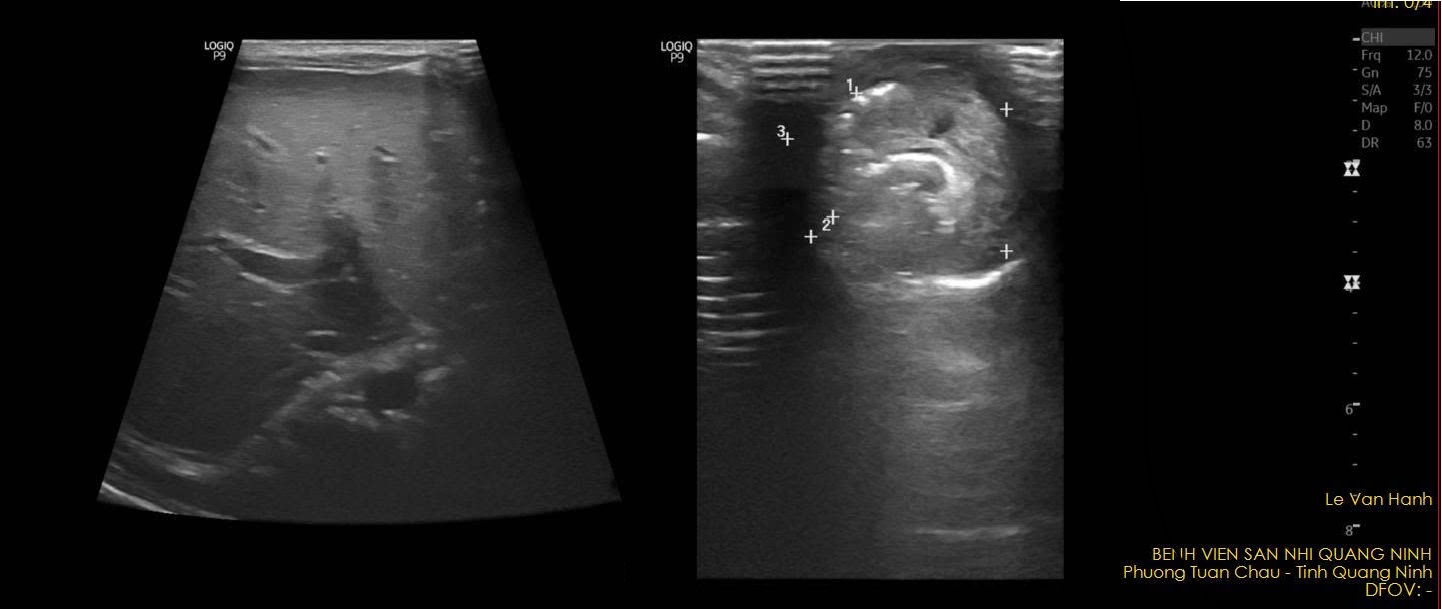

Kết quả khám và siêu âm ổ bụng cho thấy hình ảnh khối thoát vị, kích thước 21x22mm, thành phần trong khối là quai ruột có nhu động.

Quá trình phẫu thuật khi mở khối thoát vị rốn thấy tại khối thoát vị là quai ruột non, từ quai ruột non có ống nối sang rốn chảy dịch tiêu hóa. Ống niệu rốn thông thương từ ruột ra rốn được cắt bỏ, ruột non được khâu phục hồi.